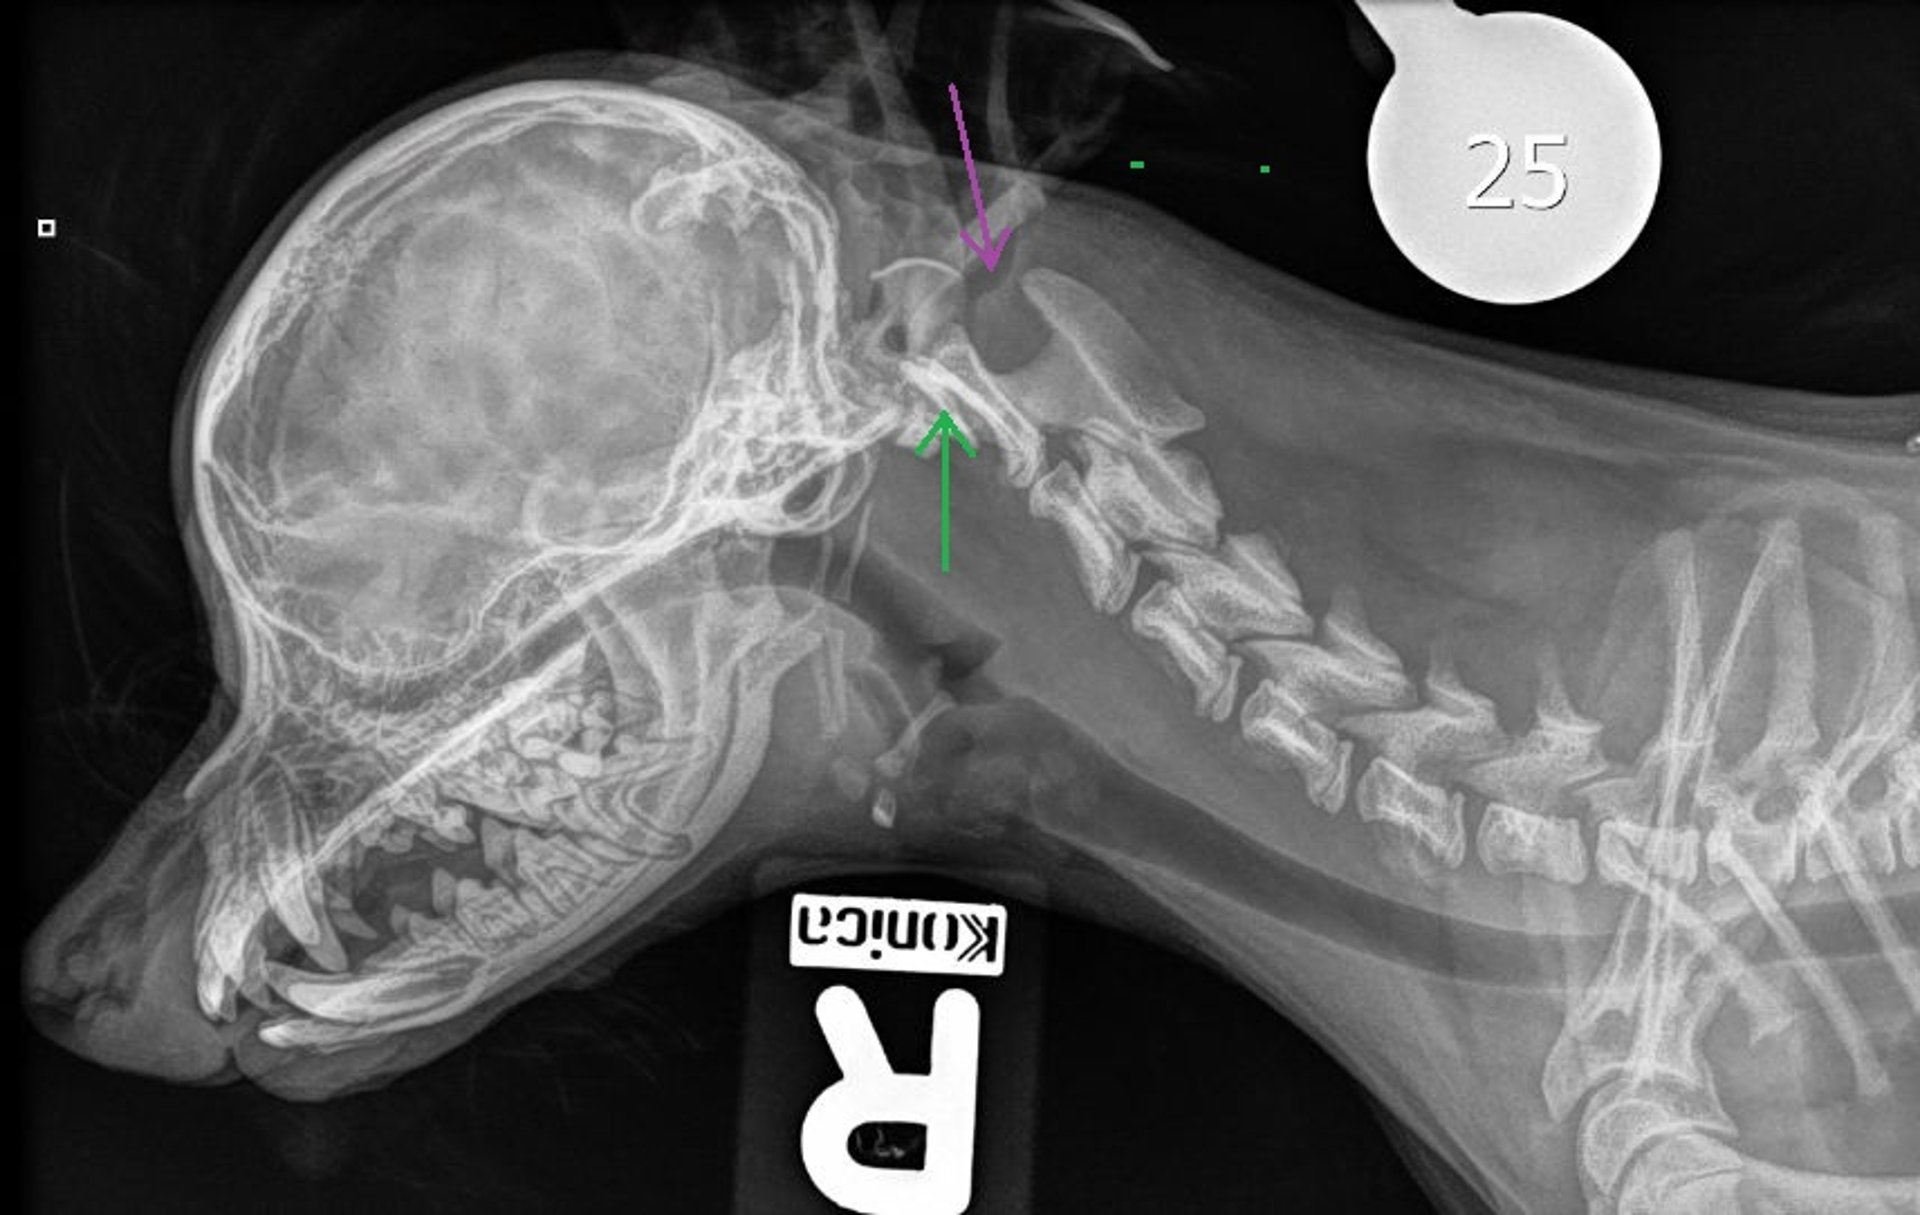

Atlantoaxial subluxation, dog, radiograph

Lateral radiograph of the cranium and cervical spine in a dog with atlantoaxial subluxation. Note the absent/aplastic dens (green arrow) and caudal dorsal displacement of C2 compared to C1 (purple arrow), with an increased angle between the dorsal spinous process of C2 and the dorsal lamina of C1.

Courtesy of Dr. Genesis Lopez Bonilla.